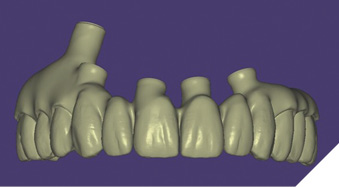

These new records along with the Nexus scans taken at the time of implant surgery were sent to Osteon Medical through the Nexus iOS portal with instructions to replicate the provisional restoration design with correct adaptation to the healed soft tissue. Three days after the data was submitted to Osteon Medical, .STL files of the final design for the maxillary and mandibular restorations were sent through the portal to our office and 3D printed in our office (Figs. 23A-C).

Fig. 23A

Fig. 23B

Fig. 23C